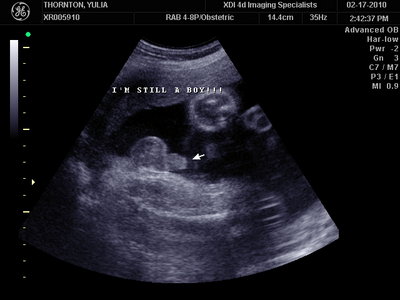

А это в 30 недель

| Вложения: |

MY BABY SONO!_20.JPG [ 94.63 КБ | Просмотров: 1112 ]

Sweetheart75 писал(а): Ну ладно, тогда и я нашего писюна покажу  Надеюсь, Джеффри на меня не обидится Вот это в 23 недели: (там оборудование переключалось из режима 3Д в обычный 2Д) Oоо, такое достоинство невозможно не заметить  А в 30 недель так вообще!